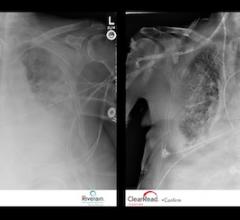

ClearRead +Confirm, new software from Riverain Technologies that improves the clarity of conventional chest X-ray images and allows radiologists to rapidly confirm the proper placement of tubes, lines and wires, has received 510(k) clearance from the Food and Drug Administration (FDA).

New software by Riverain Technologies that improves the visual clarity of conventional chest X-ray images and increases radiologists’ efficiency by reducing the time it takes to accurately confirm the proper placement of lifesaving feeding, drug-delivery and pain management tubes and lines has received CE Mark approval.